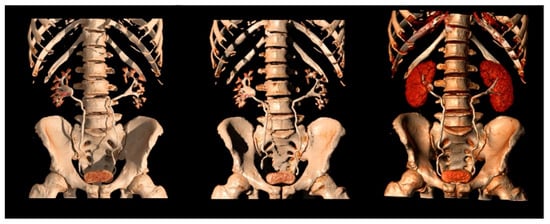

Figure 7.

Different 3D reconstructions of the excretory phase.

MIP reformations are constructed from the highest attenuation voxels in a dataset and projected into a 3D format. These reconstructions are particularly helpful in evaluating the collecting systems and ureters, allowing a complete and quick overview of the high-density contrast within the collecting systems, and highlighting subtle filling defects, focal thickening of the excretory system walls, luminal narrowing or strictures, calyceal abnormalities, hydronephrosis, and hydroureter.

Three-dimensional reconstructions provide specific colors to each voxel in a data set according to its attenuation and relationship to other adjacent voxels, allowing the visualization of the whole opacified excretory system. Some authors support their role in the identification of slight urothelial thickening, especially in cases of reduced excretion of the contrast into the collecting system, when MIP reformations are of limited usefulness [7,19,46].